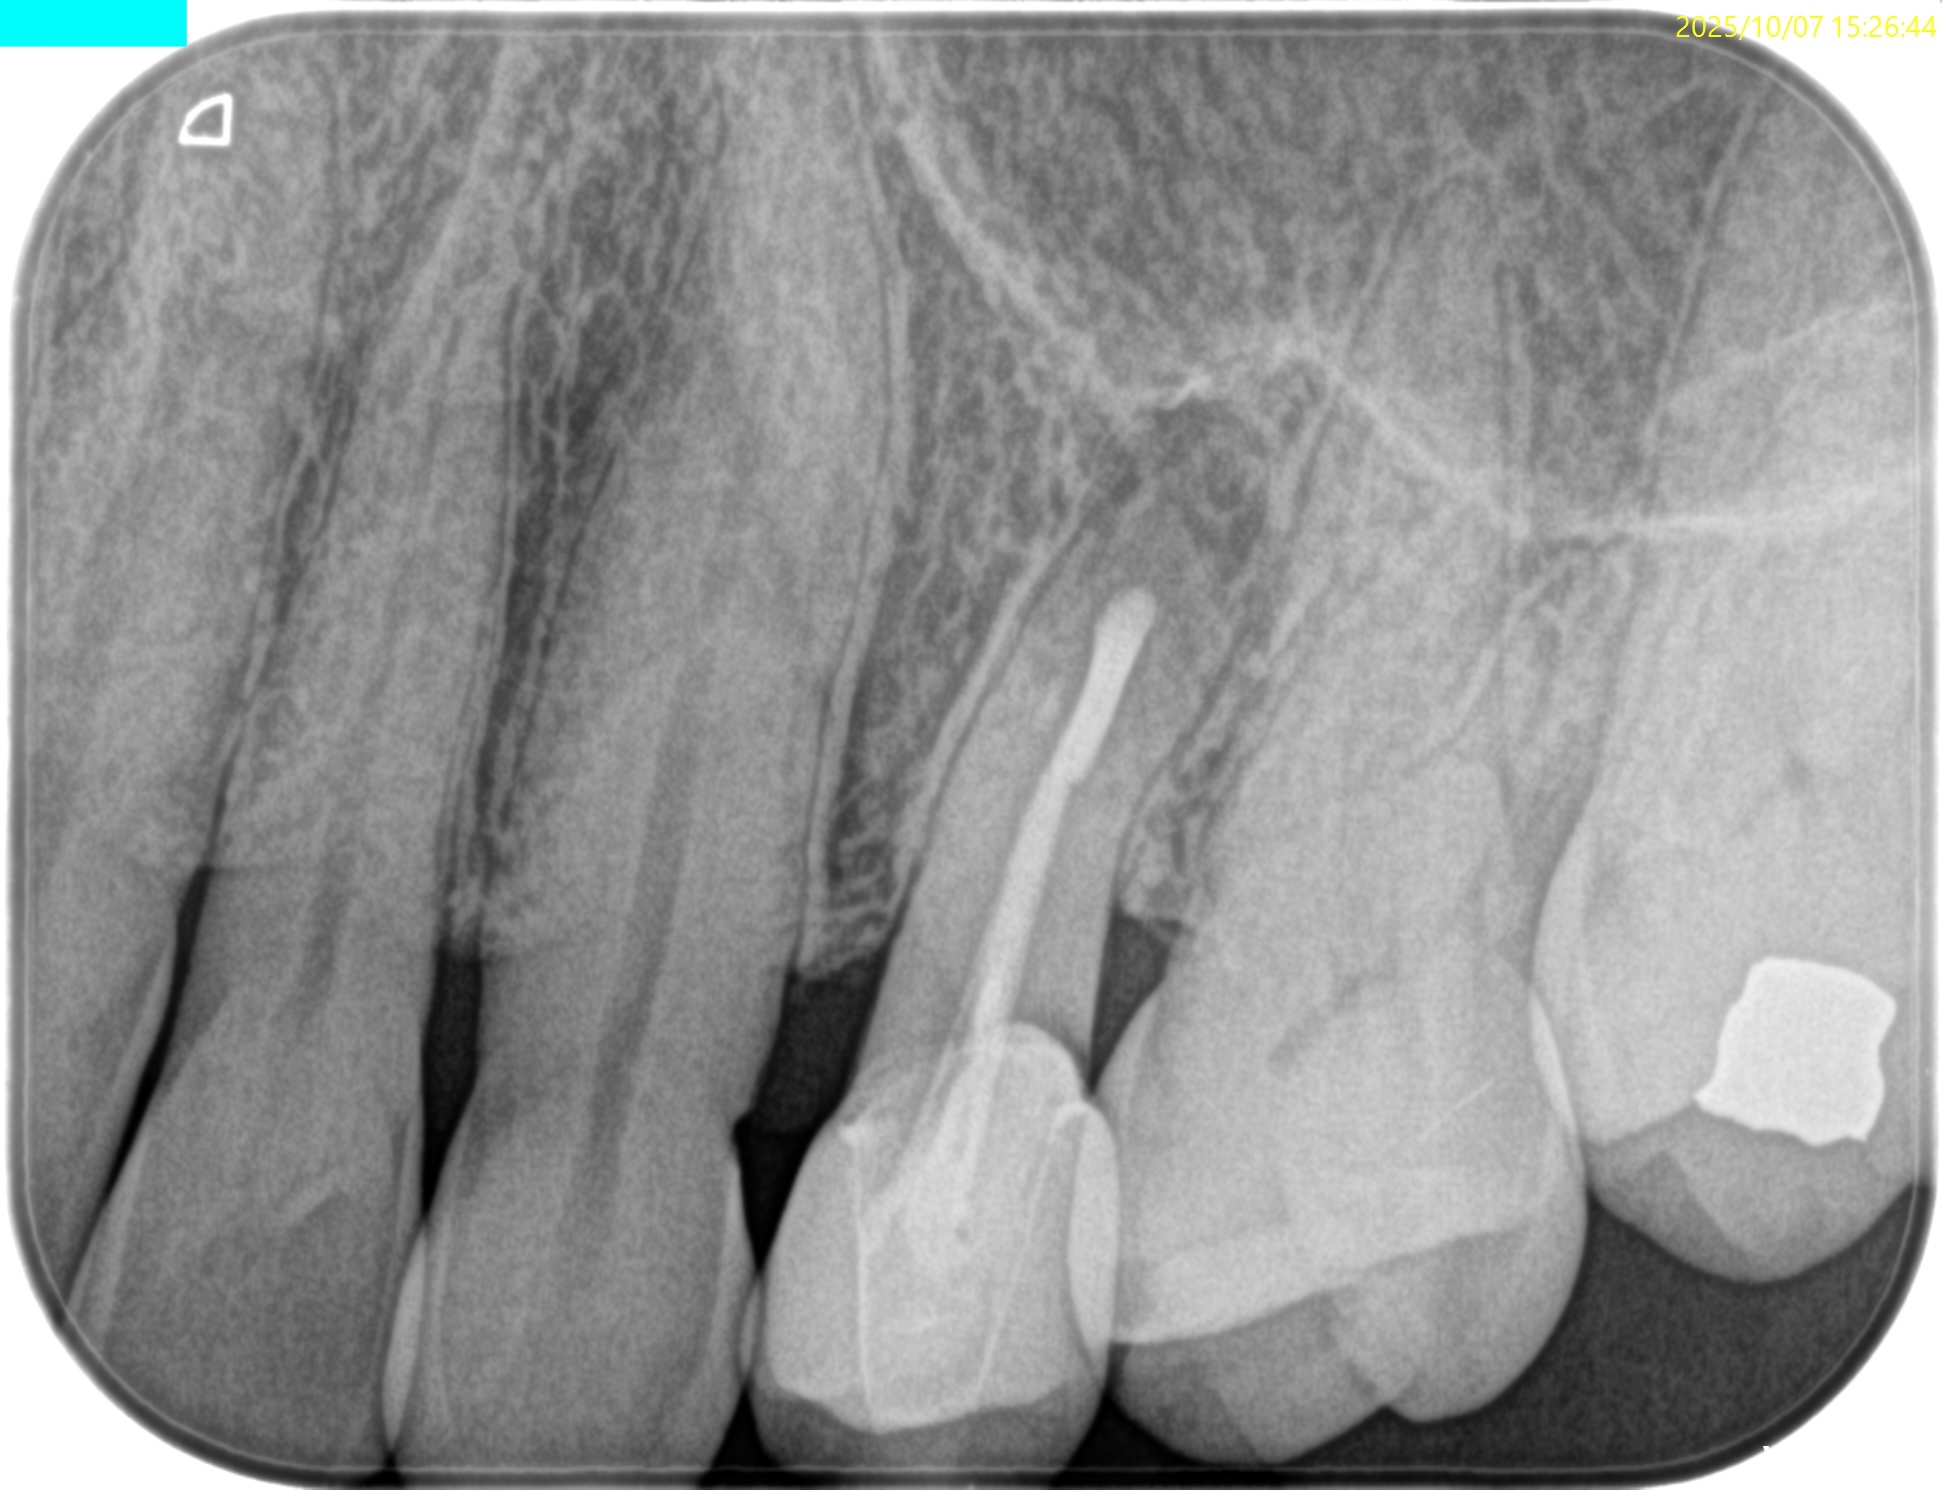

PA(2025.8.22)

もの詰まりはこの#13の遠心の築造体が剥き出しのマイクロリーケージであろう。

CBCT(2025.8.22)

#13 遠心のマージンが歯肉縁下でクラウンが不適合だ。ここにものが詰まるようだ。

これが患者さんの主訴である。